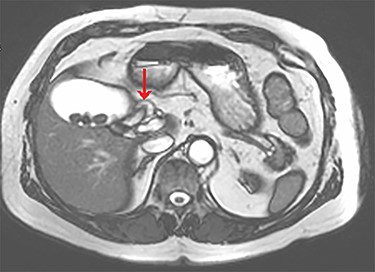

Axial view of the liver and gallbladder from a cardiac MRI showing a tubular structure entering the gallbladder at the level of the body in keeping with an accessory cystic duct (highlighted by the arrow).

The tubular structure was remote from the porta hepatis with one lumen. It was located within the distal gallbladder fossa. Inspection of the gallbladder demonstrated an opening at the same orientation and of the same calibre as this tubular structure, raising suspicion for a duplicated cystic duct. Probing the source of the bile leak confirmed a single lumen. The capacity to perform IOC was not available at the time of the operation. A review of the patient’s prior imaging was performed. Recent cardiac magnetic resonance imaging (MRI), while not dedicated magnetic resonance cholangiopancreatography (MRCP), provided adequate views of the liver, gallbladder and biliary tree to demonstrate the suspected anomaly. On these images, two structures were seen to be connecting the gallbladder to the biliary tree. One duct was observed at Hartmann’s pouch, while a second connected to the gallbladder body (Fig. 1, Fig. 2). The images confirmed suspicion of a duplicated cystic duct and the decision was made to clip the lumen. The cholecystectomy was completed and a drain placed in the gallbladder fossa.